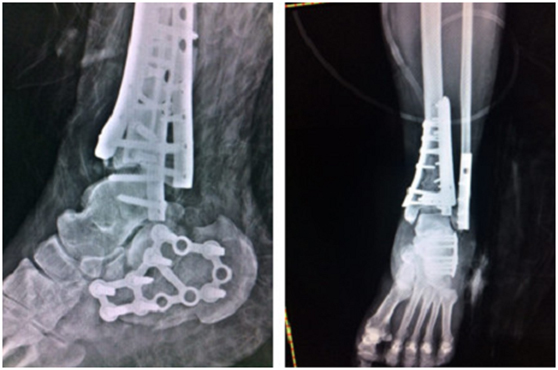

(術(shù)后)

4月上旬,俞光榮教授和足踝科徐明亮手術(shù)小組共同為華大姐進(jìn)行了“左pilon骨折及左跟骨骨折切開(kāi)復(fù)位內(nèi)固定術(shù)”,手術(shù)進(jìn)行了4個(gè)小時(shí),非常成功。

“患者是雙pilon骨折,雙跟骨骨折,腰椎部位還多發(fā)骨折,手術(shù)不能一次做完,得分期做。一次做完的話手術(shù)時(shí)間太長(zhǎng)容易感染,病人也承受不了。”徐明亮主任說(shuō)。